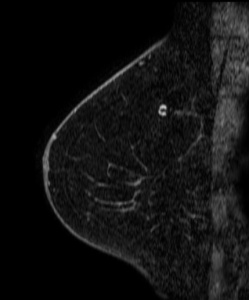

A mass is present in the upper outer quadrant of the left breast:

How is this mass best described?

A. BI-RADS 0 (Incomplete); Recommend diagnostic mammogram and ultrasound

B. BI-RADS 2 (Benign); Recommend one year follow-up

C. BI-RADS 3 (Probably Benign); Recommend six month follow-up

D. BI-RADS 4 (Suspicious); Recommend biopsy

Answer

Explanation: This is the classic appearance of an intramammary lymph node on mammography. This is a normal breast structure, typically appearing as a circumscribed small mass on the mammogram with a lucent notch that corresponds to the anatomic fatty hilum. The most common location is in the upper outer quadrant. If the appearance is not quite classic, a history of stability on prior mammograms is reassuring that this is most likely a normal/benign lymph node.

In this patient’s case, her intramammary lymph node had been unchanged for many years and has the expected appearance of a lymph node on this post-contrast MRI image: